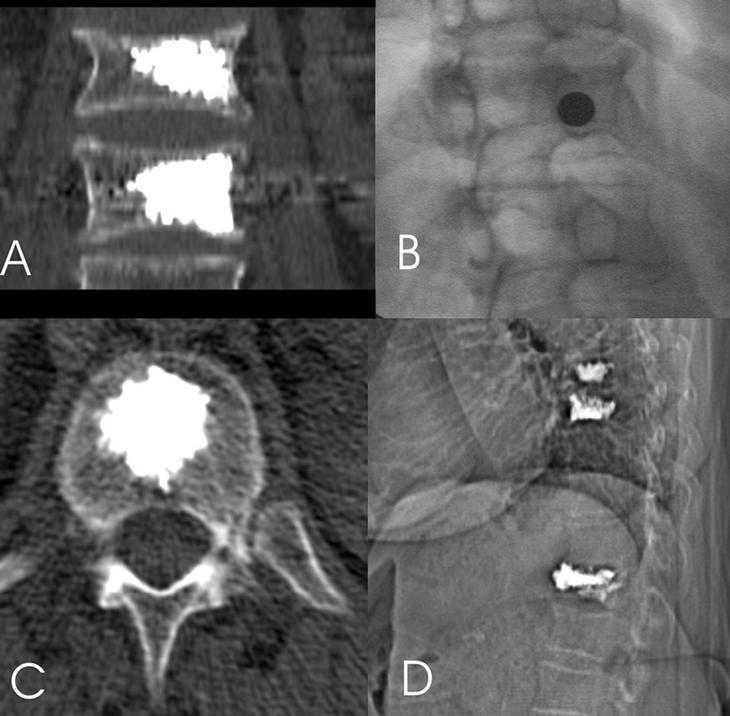

Para poder realizar el acceso laterotranspedicular es necesario que la trayectoria de la aguja, para ello se inclina el haz de rayos X hasta que la apófisis espinosa se superponga con el pedículo contralateral y el pedículo a puncionar se identifique correctamente (fig. 3).

Figura 3. A: reconstrucción con TC coronal de los cuerpos vertebrales de 2 vérterbras tratadas. B: posición oblicua para el acceso laterotranspedicular, control de la aguja perpendicular. C: control con TC de la distribución del cemento en el cuerpo vertebral. D: radiografía lateral, sea oblicua; control de vertebroplastia, 3 niveles.